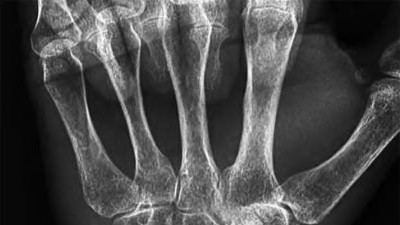

A 35-year-old woman reports wrist pain after a fall onto an outstretched hand. On exam, she has focal tenderness over the wrist snuffbox. A radiograph and CT image are shown in Figures A and B. What is the proper treatment of her injury?